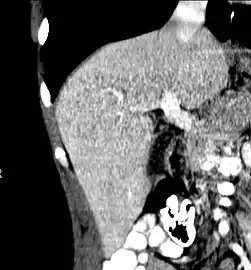

Left lobe liver tumor

The liver is a vital organ and supports almost every other organ in the body. Because of its strategic location and multidimensional functions, the liver is prone to many diseases.[52] The bare area of the liver is a site that is vulnerable to the passing of infection from the abdominal cavity to the thoracic cavity. Liver diseases may be diagnosed by liver function tests–blood tests that can identify various markers. For example, acute-phase reactants are produced by the liver in response to injury or inflammation.

After resection of left lobe liver tumor